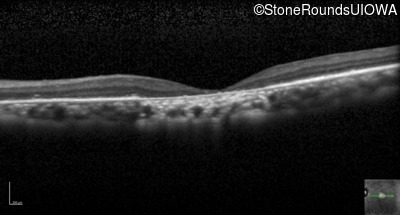

Optical Coherence Tomography - Right - 20/1250 sc

Exemplar / OCT Stack

OCT Stack

Optical Coherence Tomography - Left - 20/500 sc